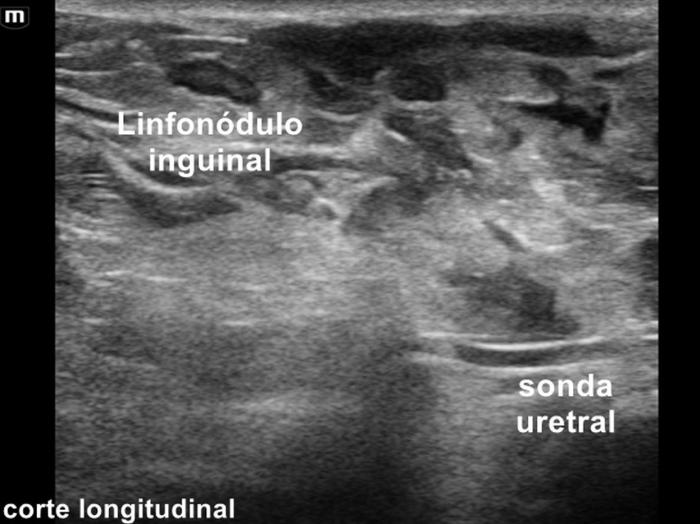

La ultrasonografía abdominal y de la cavidad pélvica permite identificar líquido libre, engrosamiento periuretral y cambios secundarios como hidronefrosis. En el caso de un paciente canino macho, muchas veces se detecta una prostatitis aguda y celulitis en el tejido subcutáneo de la región pélvica debido al contacto con la orina (Figura 1-3) (Vídeo 1). Sin embargo, rara vez demuestra de manera directa la fuga urinaria⁴.

Vídeo 1. Vídeo del paciente.